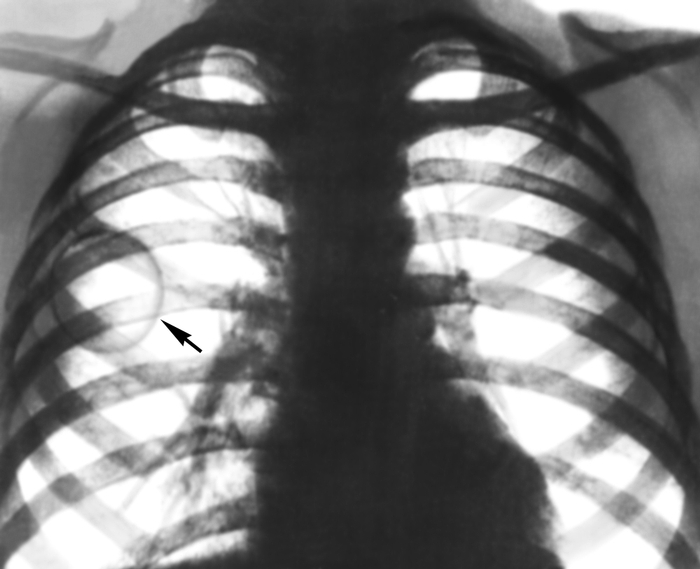

Рентгенологические изображения и синдромы патологии легких

Раздел: Кадры-подсказки